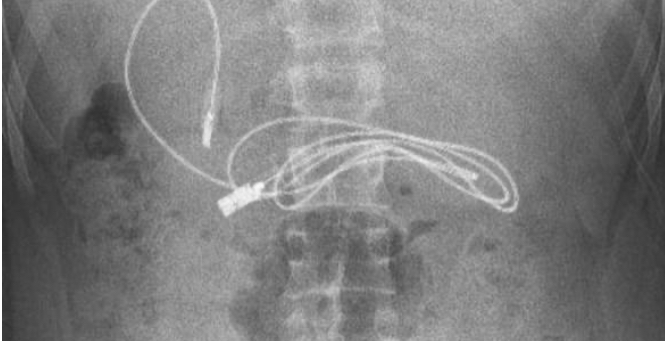

صدم مراهق الأطباء، بعد نقله إلى أحد مستشفيات تركيا وهو يعاني من غثيان شديد وآلام مبرحة في معدته، إذ أظهرت الأشعة المقطعية، ابتلاعه سلك شاحن طوله 90 صنتيمتراً.

وخضع المراهق الذي لم تكشف هويته، إلى عملية عاجلة لاستخراج السلك من معدته، ليتبين أنه ابتلع ربطة شعر، أيضاً، حسب صحيفة ميرور البريطانية.

وقال الطبيب الذي أشرف على الجراحة، إن العملية كانت معقدة لأن أحد طرفي السلك مَر إلى الأمعاء الدقيقة. ولحسن الحظ، تعافى المراهق، 15 عاماً، سريعاً بعد العملية وعاد إلى منزله في ديار بكر بصحة جيدة.